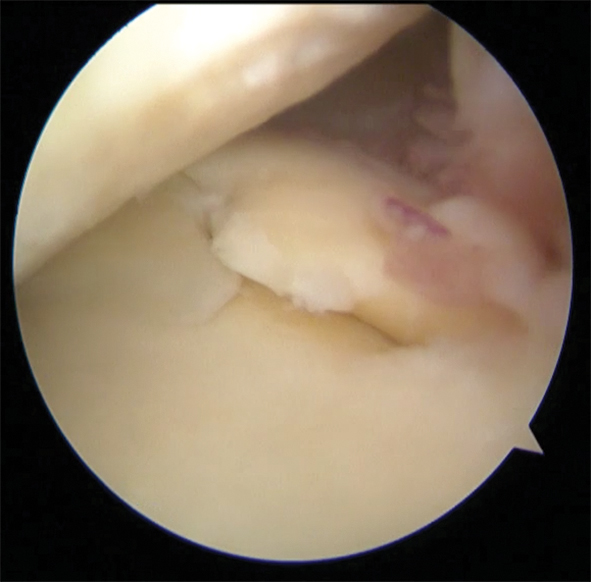

È importante la comprensione dei meccanismi di produzione delle lesioni perché il loro pronto riconoscimento consente l’adozione delle misure diagnostiche e terapeutiche più appropriate. Questa velocità di “azione” per lo sportivo riflette la necessità di ritornare in breve tempo all’attività fisica. Per il medico, la velocità nel formulare la corretta diagnosi è importante poiché può condizionare la direzione terapeutica e i risultati finali. Pensiamo ad esempio alla rottura del legamento crociato anteriore. Si tratta di uno dei 4 legamenti più importanti del ginocchio ed ha la funzione di stabilizzarlo impedendo la traslazione anteriore della tibia rispetto al femore. Questo legamento, rispetto agli altri, non ha nessuna capacità di “guarigione” e quindi il ginocchio, privato del suo stabilizzatore, risulta predisposto a subire ulteriori traumi distorsivi/cedimenti sia durante l’attività sportiva sia durante le attività del quotidiane. Per questo motivo, nel soggetto attivo, è importante intervenire adeguatamente. Un trattamento ritardato fa aumentare del 20-30% il rischio di avere un danno cartilagineo e del 70% quello di avere una lesione del menisco. Il trattamento tempestivo, inoltre, consentirà di aumentare la probabilità di salvaguardare una struttura nobile come il menisco: la meniscectomia è eseguita solo nel 48% dei casi se la ricostruzione legamentosa è praticata a breve tempo dal trauma. Del resto, oggi, l’ortopedico articolare ha come obiettivo il: “save the meniscus”. Il menisco, infatti, è una struttura nobile che partecipa alla dissipazione dei carichi articolari, alla stabilizzazione del ginocchio e alla propriocezione. È evidente l’importanza di poter “riparare” questa struttura per salvaguardarne la funzione. Se ciò non è possibile a causa del tipo di lesione, si dovrà eseguire una meniscectomia selettiva cercando di conservare la maggior quantità di tessuto meniscale. Una delle conseguenze della meniscectomia nel lungo periodo può essere una deformazione dell’asse anatomico del ginocchio (in alcuni soggetti tale deformità è congenita) con degenerazione cartilaginea. La deformità si accentua con il carico e il peso corporeo e si può aggravare progressivamente causando dolore e limitazione funzionale. Oggi nel paziente giovane attivo, la procedura più idonea per correggere questa condizione è l’osteotomia: frattura parziale della tibia o del femore, stabilizzata con placca e viti, per ottenere una correzione dell’asse di carico. Alternativa di nicchia da valutare quando sia stato asportato completamente il menisco è il trapianto meniscale. È particolarmente indicato in soggetti giovani e attivi con un danno cartilagineo non eccessivamente esteso. Il menisco da trapianto (“un ammortizzatore di ricambio”) può essere proveniente da donatore (allograft) o da tessuto biocompatibile di sintesi che sarà poi “riabitato” da tessuto biologico del paziente ricevente. In quest’ultimo caso bisogna valutare che la condizione del tessuto meniscale residuo sia adeguatamente resistente e stabile poiché rappresenta la base di “ancoraggio” della protesi meniscale biologica. In definitiva, l’obiettivo della chirurgia articolare del ginocchio è di ripristinare l’equilibrio biomeccanico dell’articolazione consentendo una ripresa delle attività limitando l’evoluzione del danno degenerativo.